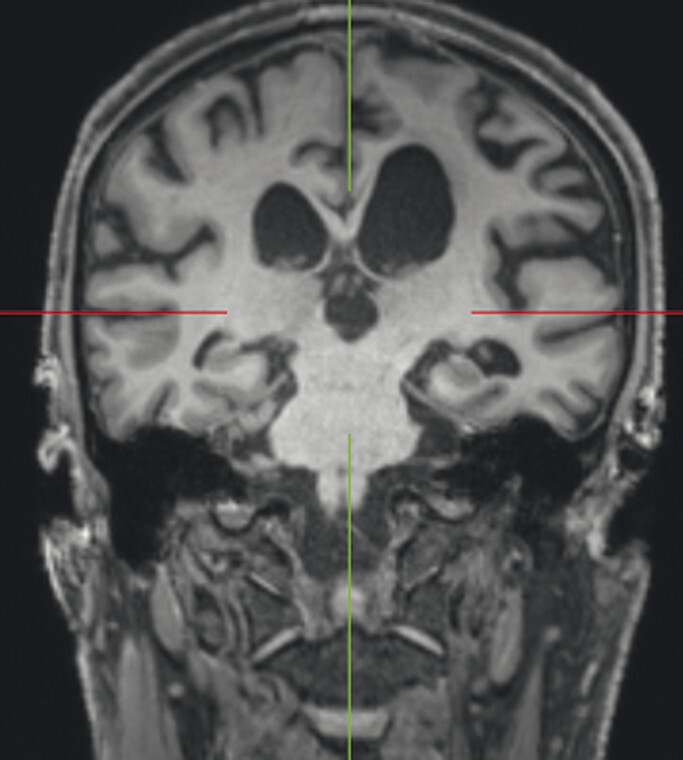

Abb. 69.11 Parkinson-Syndrome: Differenzialdiagnose kortikobasale Degeneration.

61-jähriger Mann mit rechtsbetonter Gliedmaßenapraxie, sodass Schreiben und Zeichnen nicht mehr möglich sind. MP-RAGE-Aufnahmen (a–c) zeigen eine deutliche Atrophie der linken Großhirnhemisphäre mit Ausziehung vor allem der Cella media des linken Seitenventrikels. Die voxel- und regionenbasierte morphometrische Analyse (d) bestätigt die Atrophie mit Betonung des Parietallappens. Die FDG-PET (e) zeigt einen Hypometabolismus der linken Hemisphäre mit Beteiligung von Thalamus und Basalganglien. Klinische Symptomatik und Bildgebung sind passend für eine kortikobasale Degeneration.

a Sagittale MP-RAGE-MRT-Sequenz.

b Axial reformatierte MP-RAGE-MRT-Sequenz.

c Koronar reformatierte MP-RAGE-MRT-Sequenz.

d Voxel- und regionenbasierte morphometrische Analyse.

e FDG-PET. (mit freundlicher Genehmigung von Prof. Dr. Dr. P.T. Meyer, Klinik für Nuklearmedizin Uniklinik Freiburg)